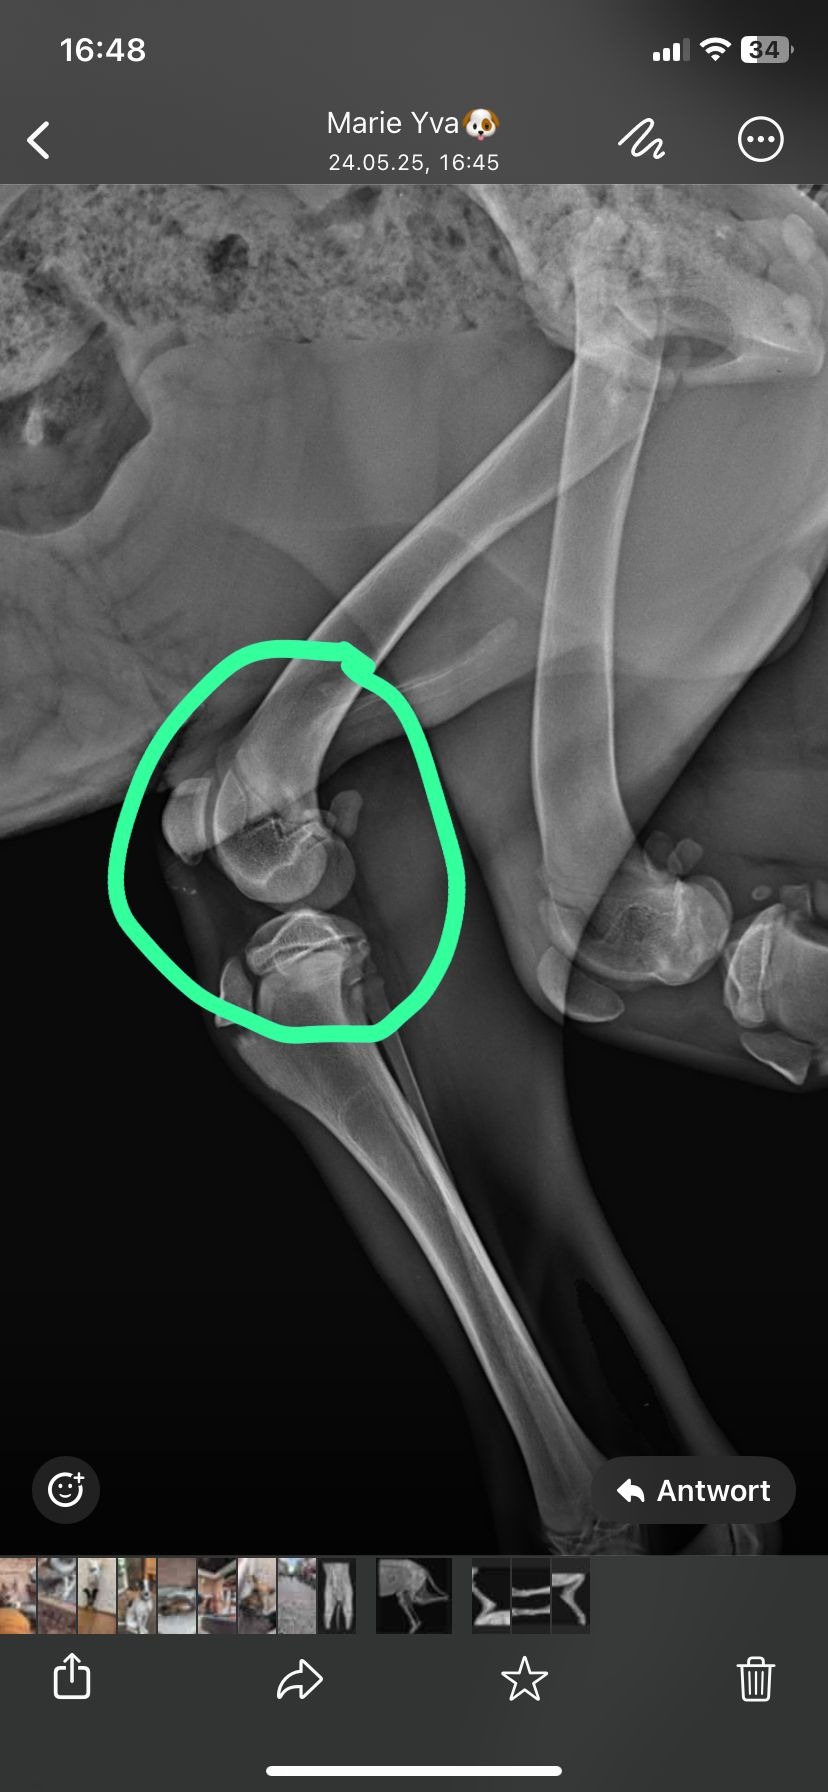

Als Welpe wurde Meeko in Rumänien, seinem Herkunftsland, verletzt von der Organisation vorgefunden. Er wurde von einem LKW angefahren und vor allem die linke Seite seines Körpers wurde lädiert. In einer Operation wurde das linke Vorderbein versteift, sodass er es heute als Krücke benutzen kann. Leider besteht zum jetzigen Zeitpunkt der Verdacht, dass auch Meekos linkes Hinterbein behandelt und stabilisiert hätte, werden müssen, da er dieses nicht natürlich benutzt und eine Fehlhaltung einnimmt. Ein aus Rumänien stammendes Röntgenbild mit der unbehandelten Fraktur im linken Hinterbein zeigen wir unter "Bilder".

Leider hat sich der ursprüngliche Verein, über den Meeko nach Deutschland kam, aus seiner Verantwortung zurückgezogen, auch in Hinblick auf die Kosten der medizinischen Versorgung, die verdachtsmäßig aus einer mangelhaften Versorgung im Herkunftsland resultieren (anhand dort entstandener Röntgenbilder belegbar). Wir als ehemalige Mitglieder*innen kämpfen nun auf eigene Faust für Meeko – doch ohne Vereinsmittel. Deswegen bitten wir euch um Unterstützung.